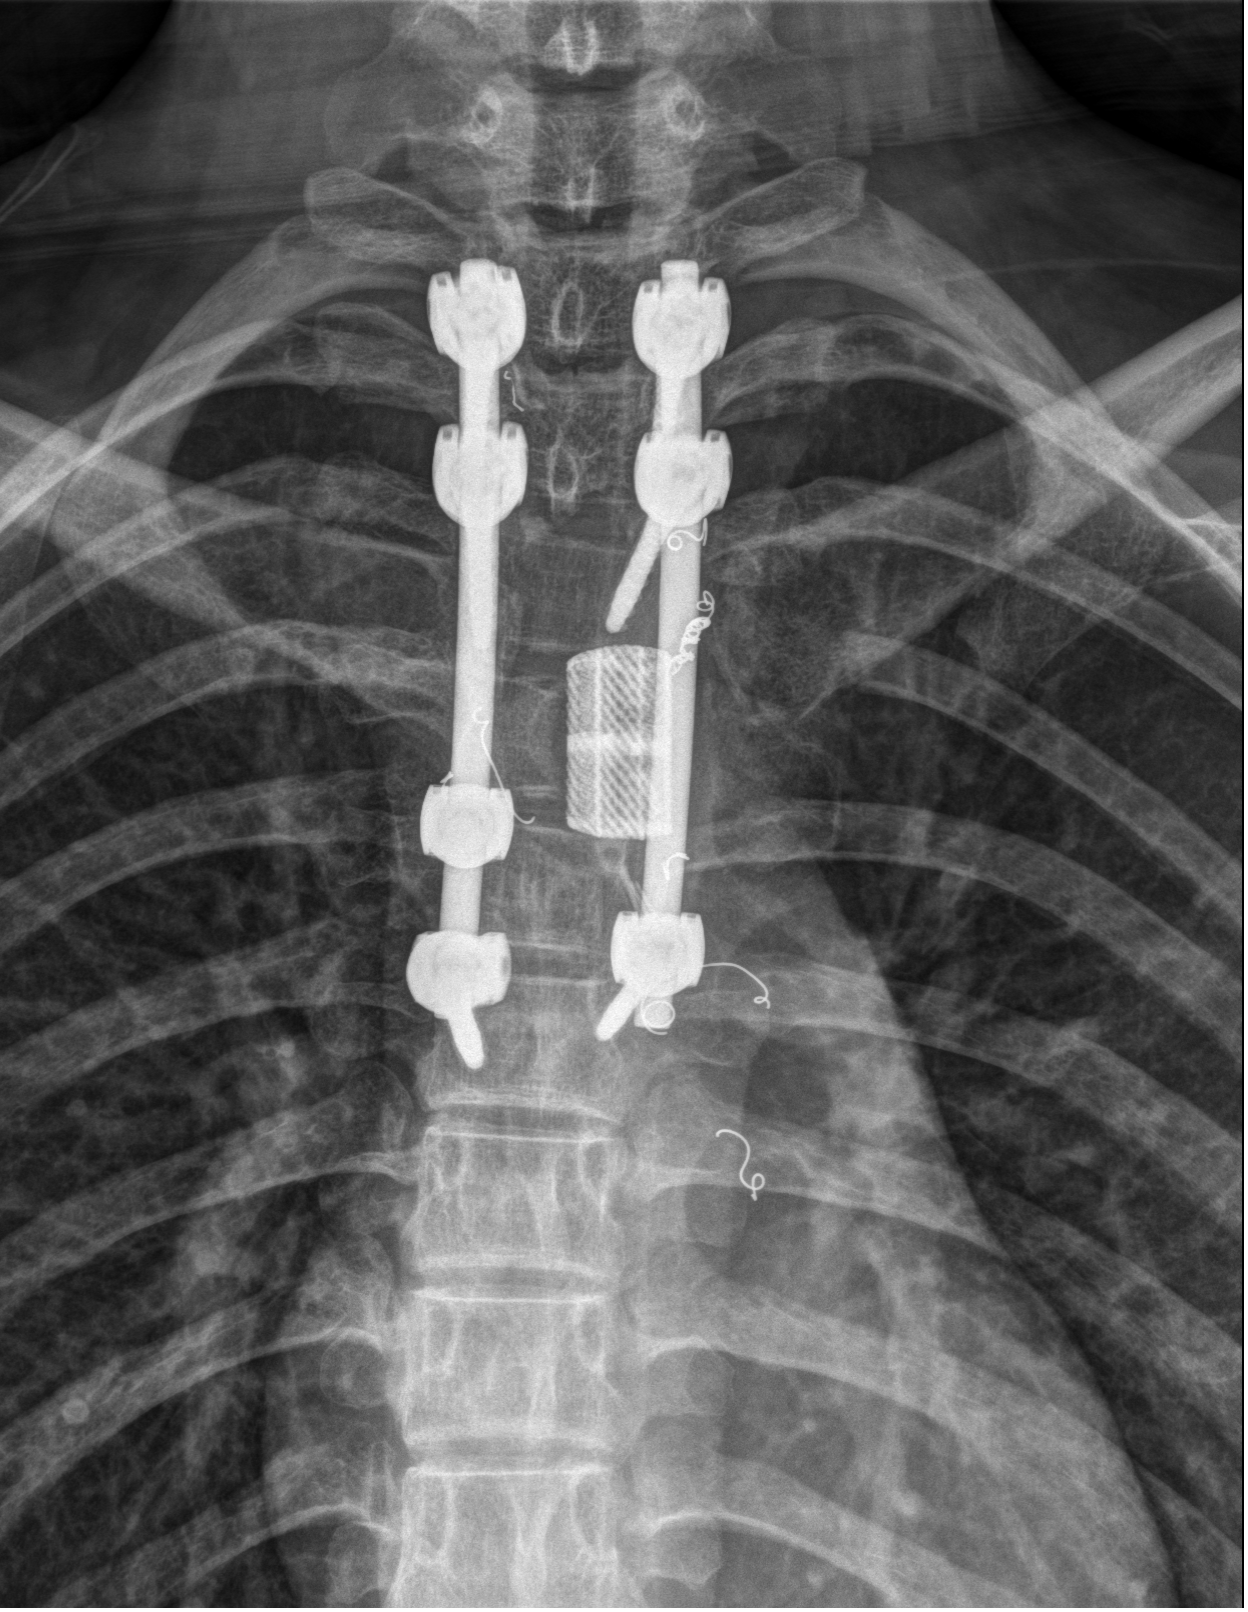

介入手术后的最佳时间窗内,脊柱外科(骨四科)手术团队接力上台。正如术前预判,因为血供被有效阻断,肿瘤实质相对缺血、质地更韧,与周围组织的边界也更清晰。

术中,主刀医生发现手术野的渗血量较未栓塞病例显著减少,视野清晰,为精细分离肿瘤、保护紧邻的脊髓和神经根创造了极其有利的条件。最终,团队成功完整切除了侵犯椎体、附件及肋骨的肿瘤,并顺利完成了椎体重建内固定术,用钉棒系重新稳定了患者的脊柱。

当手术结束时,统计出的出血量让整个团队倍感欣慰:全程出血仅约800毫升!这与以往同类手术动辄3000毫升以上的出血量相比,下降了超过70%。出血量的大幅减少,极大降低了术中输血的需要及相关风险,也为患者术后快速康复奠定了坚实的基础。